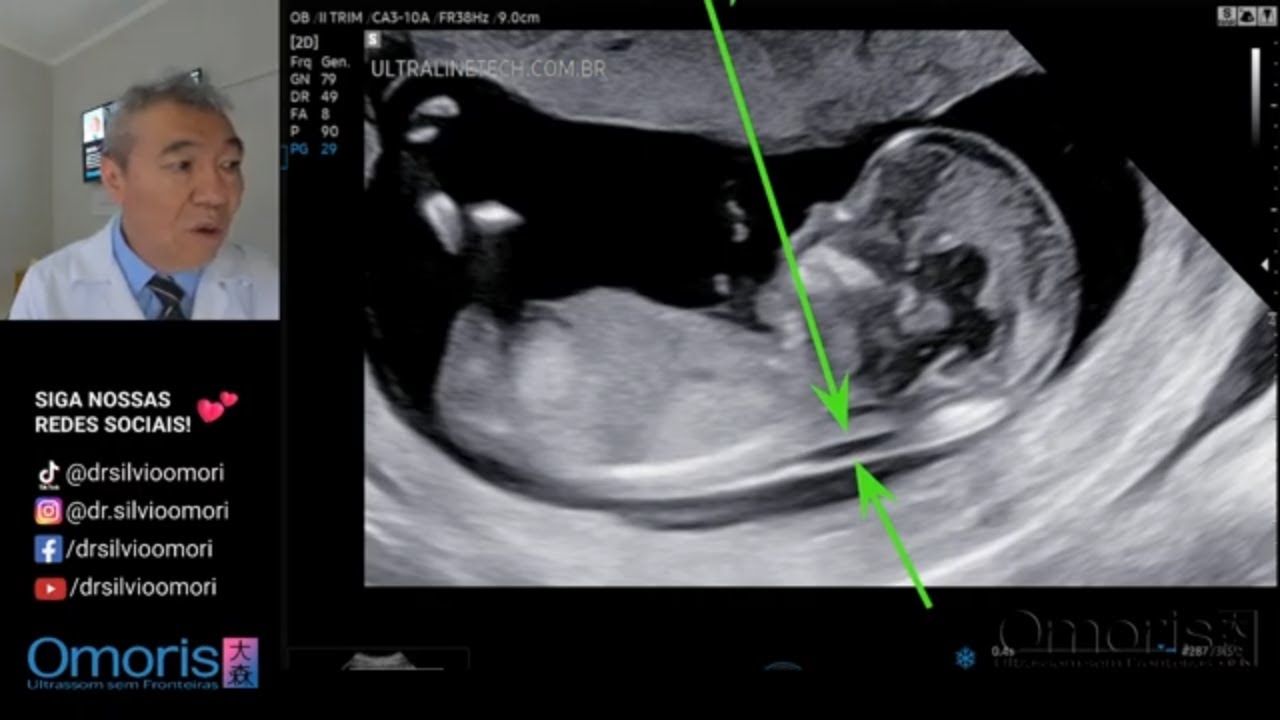

Translucência Nucal -12 SEMANAS скачать в хорошем качестве

Translucência Nucal -12 SEMANAS

Dr. Silvio Takao Omori CRM-PR 8227 RQE 27208 Instagram:   / dr.silvioomori   Facebook:   / drsilvioomori   TikTok:   / drsilvioomori   https://api.whatsapp.com/send?phone=5... #gravidez #gestante #ultrassom #gestacao #sexagemfetal